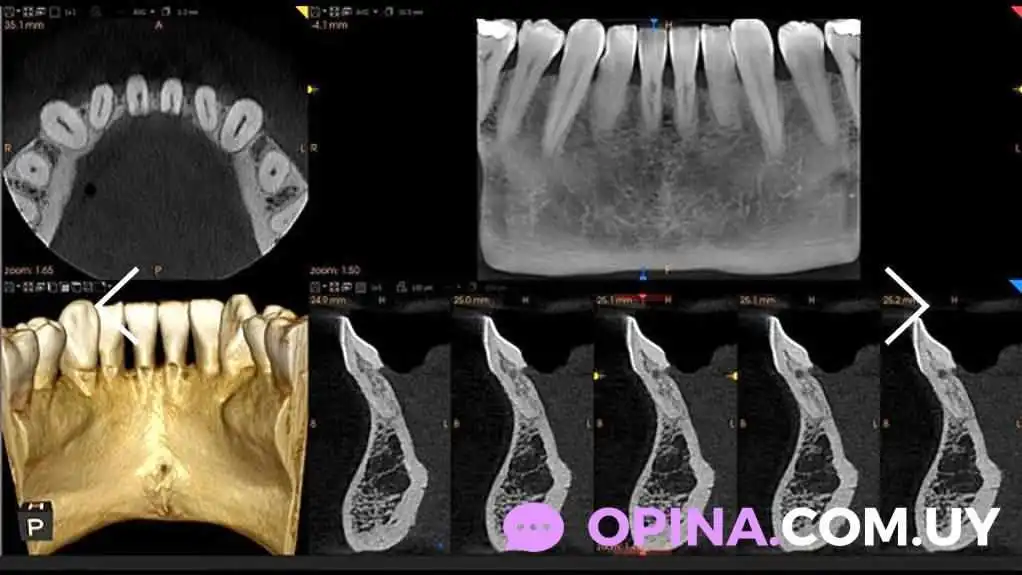

Radiología Odontológica en Cio Clínica de Imagen

La radiología odontológica es una herramienta fundamental en el diagnóstico y tratamiento de diversas patologías dentales. En este contexto, la Cio Clínica de Imagen, dirigida por el Dr. Gabriel Ruiz Figares, se destaca en San José de Mayo, Departamento de San José.

La radiología permite a los odontólogos obtener imágenes precisas de la estructura dental y de los tejidos circundantes. Esto es esencial para identificar problemas como caries, infecciones y enfermedades periodontales, así como para planificar tratamientos más complejos.

En la Cio Clínica de Imagen, se ofrecen diversos servicios relacionados con la radiología odontológica, tales como:

• Radiografías periapicales

• Radiografías panorámicas

• Tomografías computarizadas

Equipo y Tecnología Avanzada

El Dr. Gabriel Ruiz Figares cuenta con tecnología de última generación que garantiza la calidad y seguridad de las imágenes obtenidas. Esto permite realizar diagnósticos más acertados y eficaces.